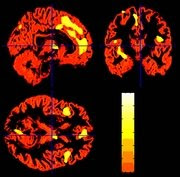

Areas in the brain that has minor volume of grey matter, among those who were in the nearness of the terrorist-attack. All areas, which are light in colour on this picture, are areas that are connected with emotions. (Foto: Barbara Ganzel/Cornell University)

”Traumas can change the brain” was the heading to an article I got a link to. It stands that evil experiences as those happening September 11 at World Trade Center can reduce the amount of grey matter in the brain. See "Resilience after 9/11: Multimodal neuroimaging evidence for stress-related change in the healthy adult brain" andBrain's gray cells appear to be changed by trauma of major events like 9/11 attack, a study suggests.